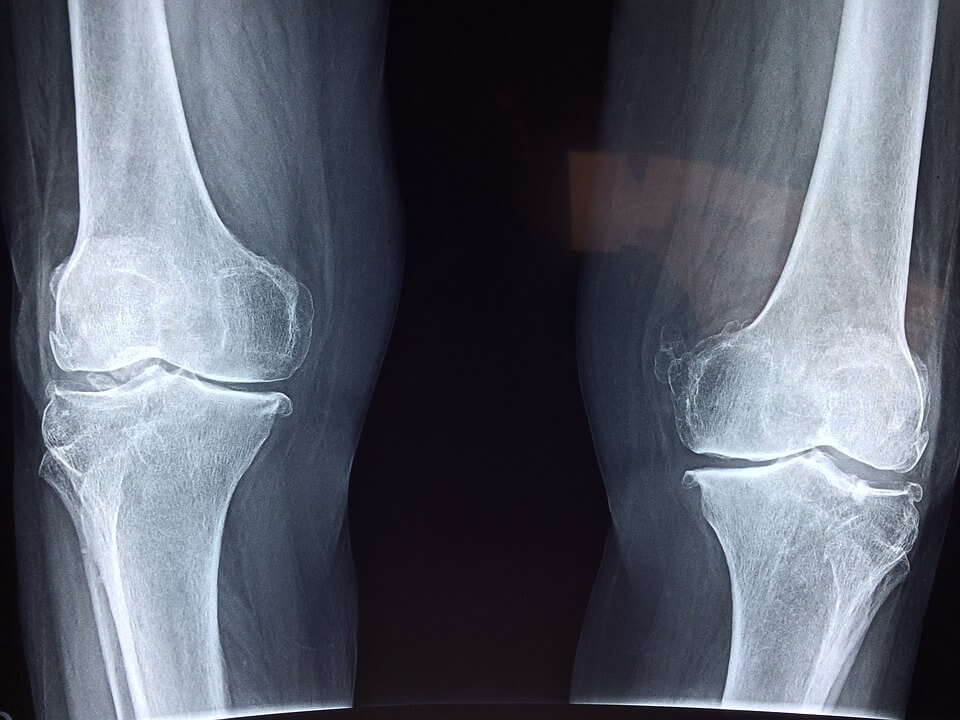

무릎관절염

무릎 관절의 연골, 뼈, 인대, 주변 조직의 염증으로 인해 발생하는 질환입니다. 무릎관절염은 노화, 관절 부상, 비만 등의 요인으로 발생할 수 있으며, 무릎 관절 주변 부위에서 심한 통증이 발생합니다. 이 통증은 일상생활에서 걷거나 계단을 오를 때 더욱 심해질 수 있습니다. 무릎 관절의 굳어짐은 일어날 때, 앉을 때, 장시간 앉아 있을 때 더욱 심해집니다. 무릎 주변 부위에 부종이 발생합니다. 부종은 통증과 함께 나타나며, 관절의 가동 범위를 제한할 수 있습니다. 무릎 관절에서 뼈가 마찰할 때 소리가 날 수 있습니다. 만성적인 무릎관절염은 무릎 관절에 변형을 일으킬 수 있습니다. 이 변형은 관절의 가동 범위를 제한하고, 보행에 문제를 일으킬 수 있습니다. 무릎관절염은 증상이 점진적으로 나타날 수 있으므로, 초기 증상이 발견되면 적절한 치료를 받아야 합니다. 적절한 치료 없이 무릎관절염을 방치하면 관절의 손상과 변형이 진행될 수 있습니다. 따라서 증상이 발견되면 즉시 의료 전문가와 상담하여 치료 방법을 결정하는 것이 좋습니다.